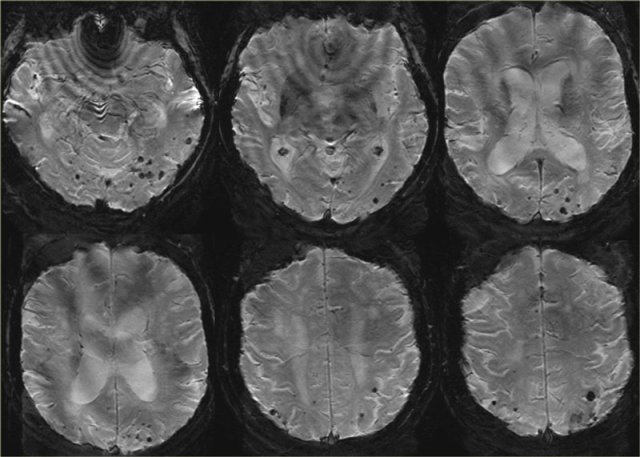

Cerebral Amyloid Angiopathy (CAA)

Dementia may be the clinical presentation in CAA, a condition in which ?-amyloid is deposited in the vessel walls of the brain.

The result is hemorrhage, usually microhemorrhages, but also subarachnoid hemorrhage or lobar hematomas may occur.

On MR, the T2* sequence will show multiple microhemorrhages, typically in a peripheral location (as opposed to hypertensive microhemorrhages, which are usually more centrally located, e.g. in the basal ganglia and thalami).

In addition, FLAIR will reveal moderate to sever white matter hyperintensities (Fazekas grade 2 or 3)

T2* images in a patient with CAA show multiple peripherally located microbleeds.

FLAIR images of the same patient show Fazekas 2 white matter hyprintensities.

T2* images in a patient with CAA microbleeds.

T2* images demonstrate multiple lobar microbleeds in a patient with CAA.